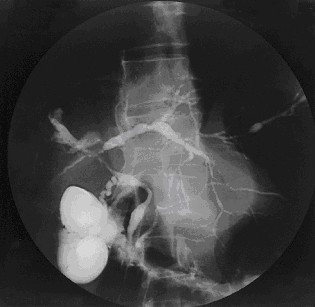

Primary Sclerosing Cholangitis

Primary sclerosing cholangitis (PSC) is inflammation and fibrosis of intrahepatic and extrahepatic bile ducts.

Primary sclerosing cholangitis (PSC) has a periductal fibrosis with an onion-skin appearance.

On contrast imaging, uninvolved areas expand, giving them a beaded look.